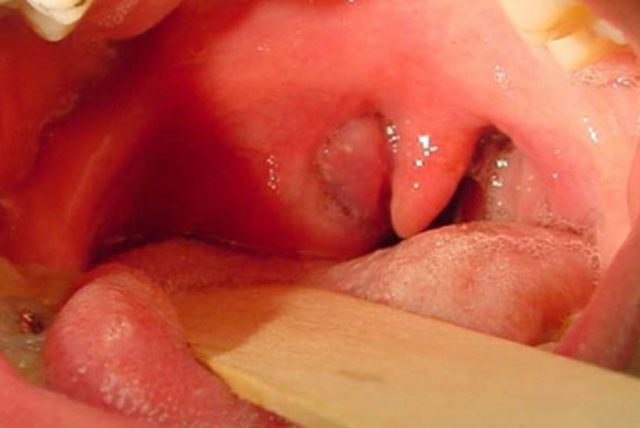

Фото

Паратонзиллярный абсцесс фото горла

фото симптомов паратонзиллярного абсцесса

Паратонзиллярный абсцесс: фото

Как выглядит данное заболевание, предлагаем к просмотру подробные фото.

- Фарингоскопия. Наиболее информативный метод диагностики. Позволяет визуально определить наличие флюктуирующего шаровидного выпячивания околоминдаликовой клетчатки, покрытого гиперемированной слизистой оболочкой. Часто на его поверхности имеется небольшой участок желтоватого цвета – зона будущего прорыва гнойных масс. Образование может вызывать асимметрию зева – смещение язычка в здоровую сторону, оттеснение небной миндалины. Локализация гнойника зависит от клинической формы патологии.

Абсцесс имеет вид круглого образования красного цвета, через поверхность которого просвечивается желтое содержимое. При пальпации некоторый участок образования будет мягким из-за содержания в нем гноя. Зев при этом смещен в противоположную абсцессу сторону.